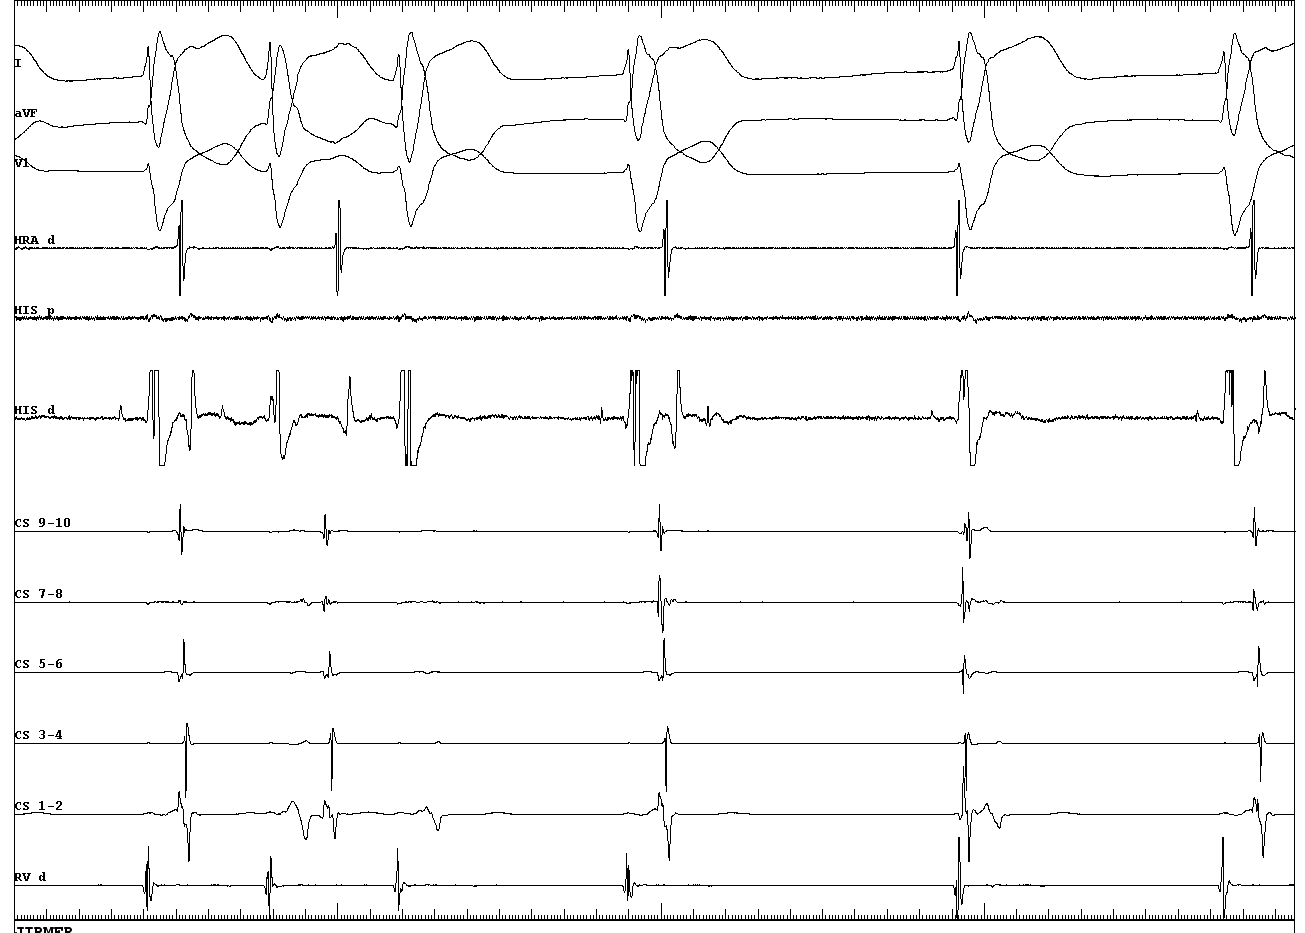

Retrograde His activation with short, fixed VH

03_VH_change.JPG